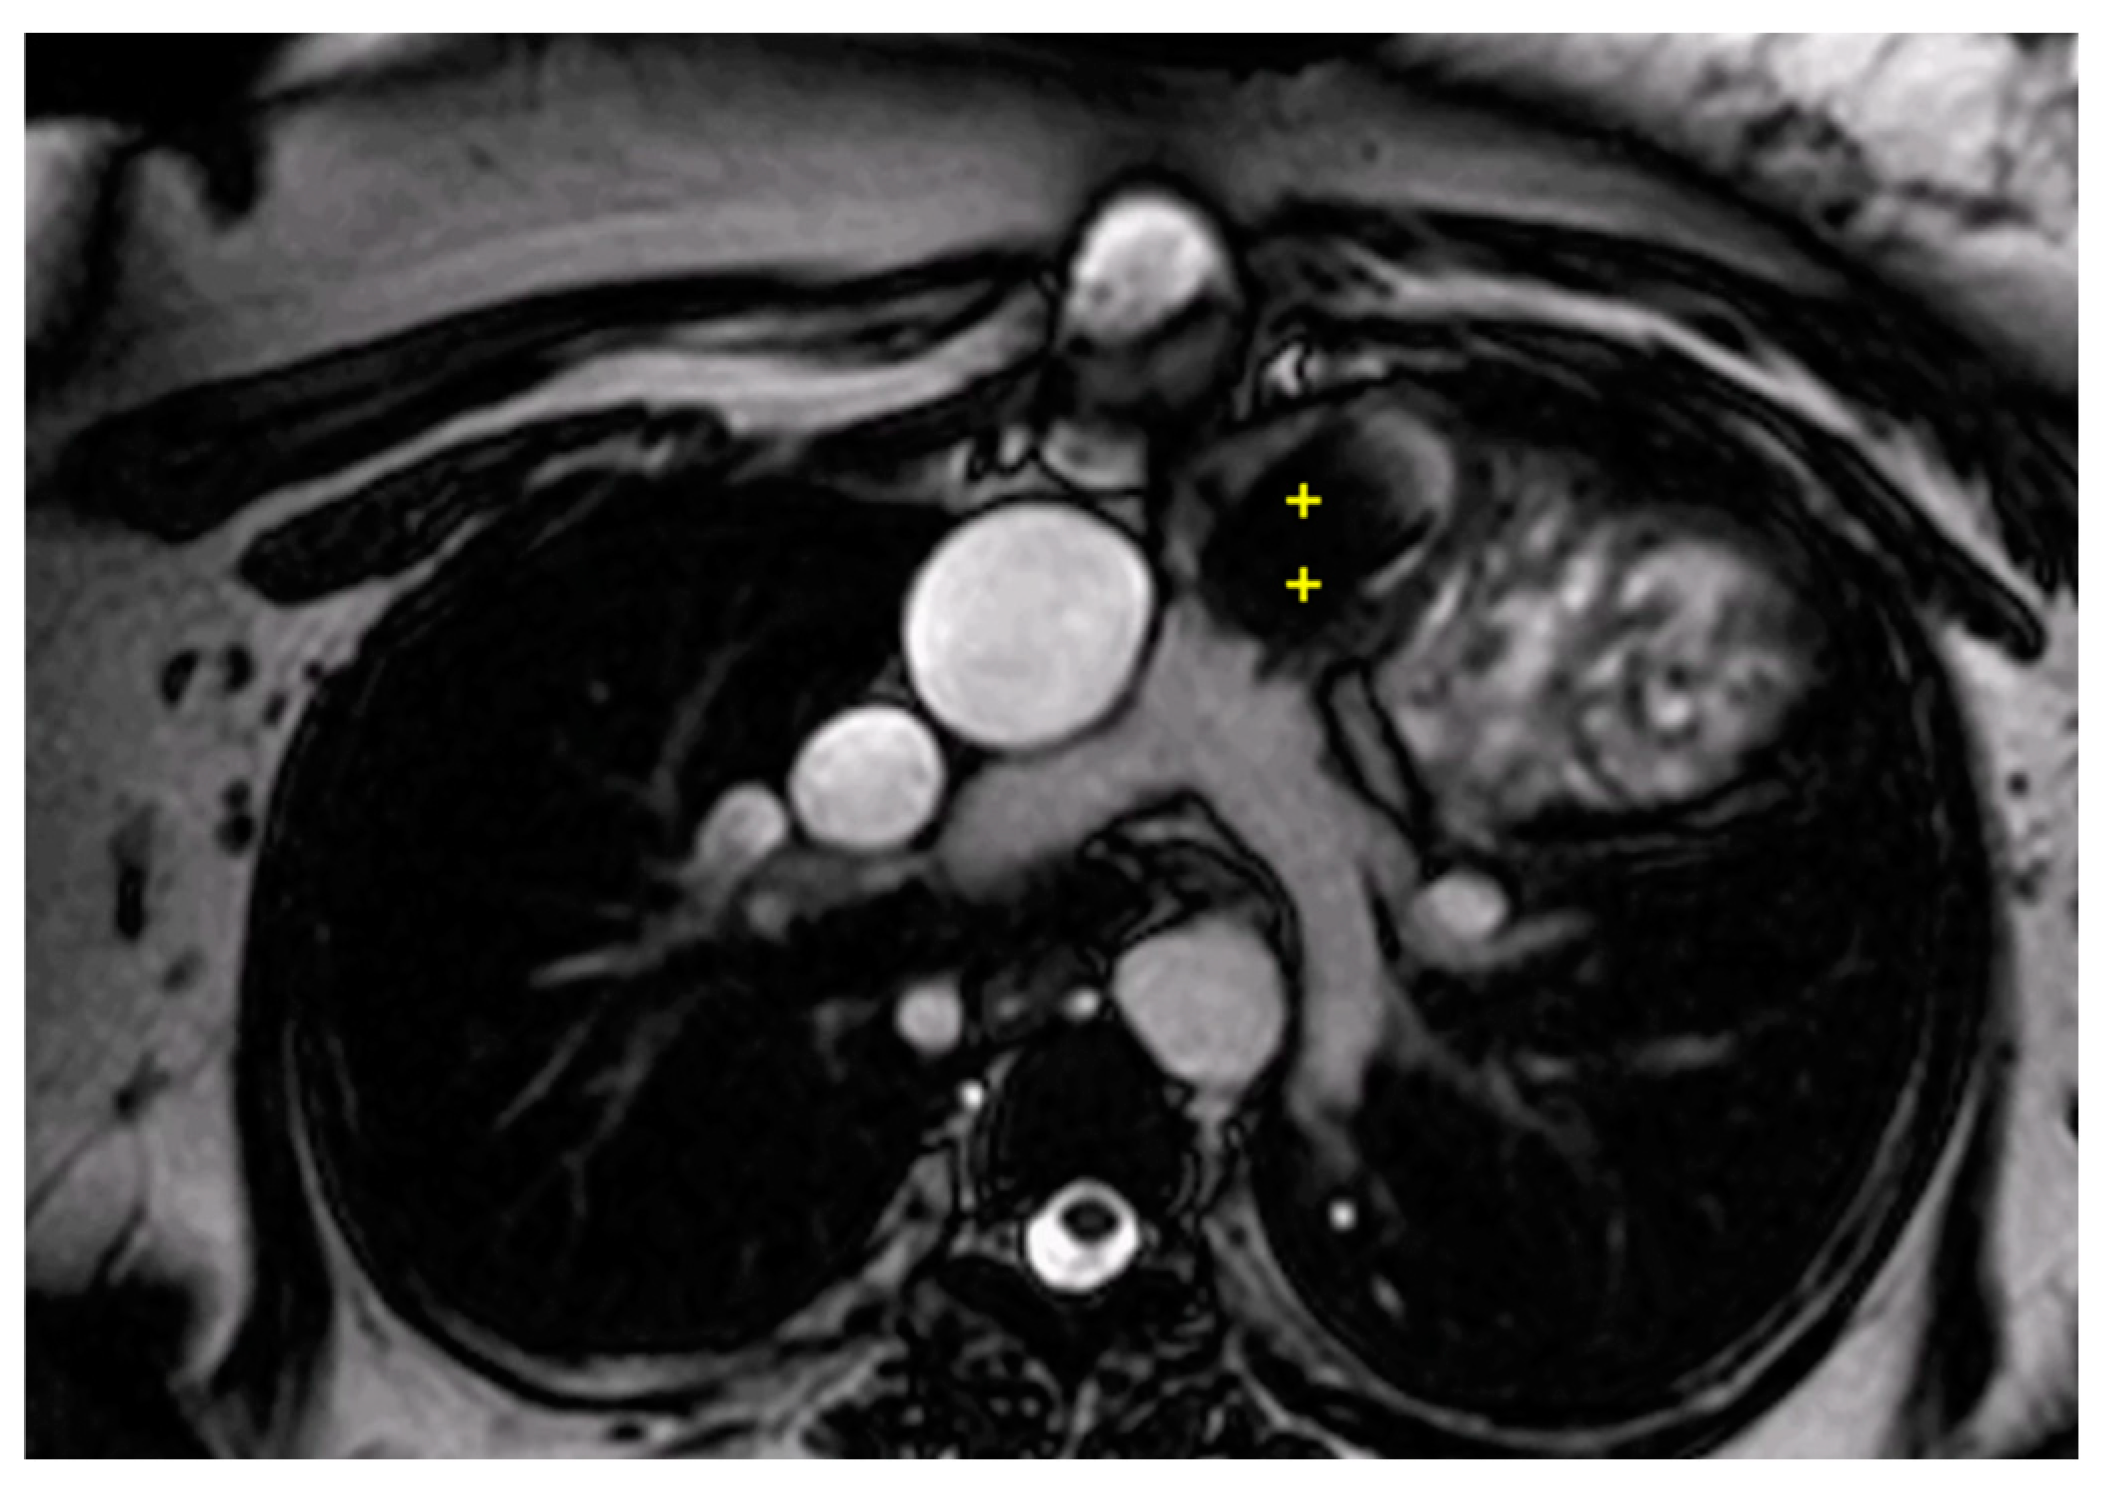

2.2.2. Congenitally Corrected Transposition of Great Arteries (cc-TGA)